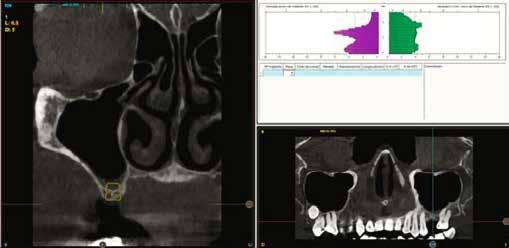

A CT metszetekben a 48-as gyökerei körbeölelik a canalis mandibularist, amelyet piros nyíllal jelöltünk a fotókon.

Szeretnék mutatni néhány ábrát az egyik bonyolult esetről, a közelmúltból. A CT-n látszik, hogy a három gyökér teljesen „körbenőtte” az ideget. Van olyan frontális metszeti kép, ahol csak a gyökerek vannak a nervus körül, ezen a szakaszon egyáltalán nincs meg a csontos fala a canalisnak. Szeparációs technikával, viszonylag könnyen, minimális traumával, szövődménymentesen sikerült eltávolítani a fog minden részét. A várakozásnak megfelelően, a beteg nem számolt be paraesthesiáról.